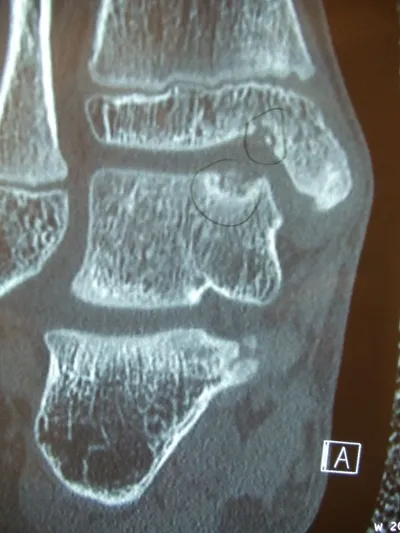

Series of Pics of Microfracture of large OCD of the Talar Dome

Pic of OCD after preparation and debridement .

Measuring the size and depth of the OCD.

Action shot of microfracture of talus OCD.

Bleeding of OCD after microfracture.